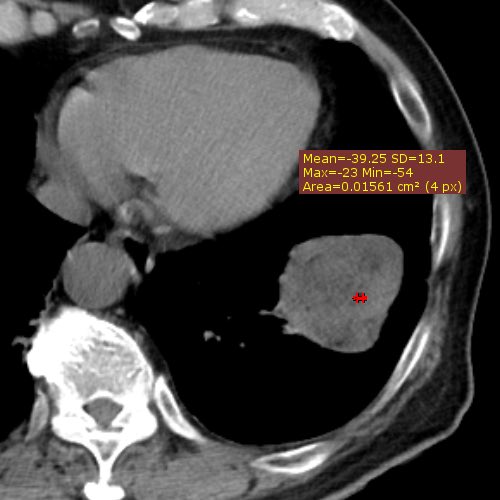

CT上吸収域が低い末梢の境界明瞭な分葉状の辺縁を有する結節として認められ

特徴としてはポップコーン様の石灰化が言われていますが、出現頻度は低く

22%程度と言われ、吸収域の低さは -33HU を閾値として採用した場合の

精度、感度、特異度はそれぞれ、95%, 100%, 96% と言われ

過誤腫の検出能力が構造する可能性が言われています。

Hochhegger B, et al. J Thorac Imaging. 2016 Jan;31(1):11-4

当院の症例では初診時はCT値の低そうなところを測定しても−24HU程度で

その報告の閾値では診断が困難でした。画像的には淡い点状石灰化も含まれており

CT値も比較的低かったので、読影者は過誤腫と読影しています。

大きくなってからは、CT値が-30HUを下回る低吸収域を示す部分が

まだら状に混在し、ポップコーン様の粗大な石灰化も明瞭に認められ

診断は容易となっています。かなり増大したという点が手術をした理由です。